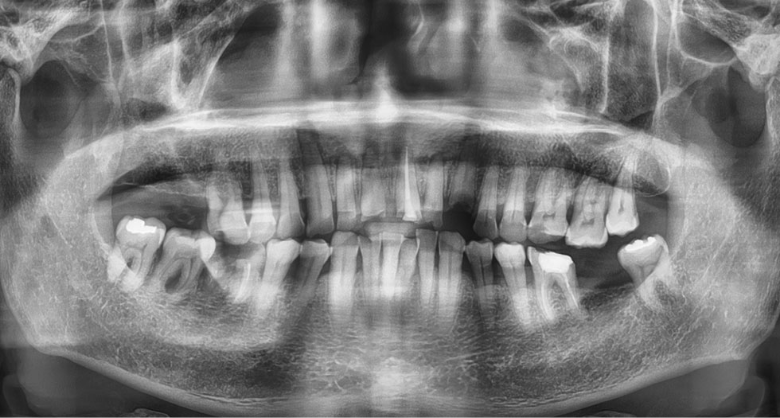

치과 임플란트란 치주 질병이나 충치, 외상 등

다양한 원인으로 치아가 빠진 부위의 턱뼈에

금속 나사를 박아서 원래 치아의 씹는 기능뿐만

아니라 심미적인 면도 회복시켜 주는

치과 인공 대체물을 말합니다.

현재 상실된 치아를 치료할 때 먼저 고려되는

방식으로 씹는 힘이 자연 치아와 비슷해서

제2의 영구치라고 평가받고 있습니다.